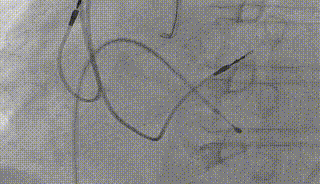

右冠保护